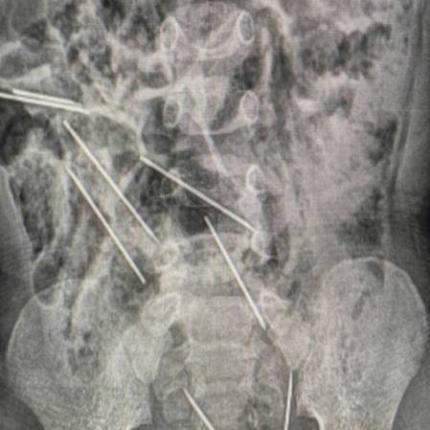

Άνοιξαν την κοιλιά του παιδιού και βρήκαν μεταλλικά κομμάτια τα οποία στη συνέχεια διαπίστωσαν πως ήταν βελόνες